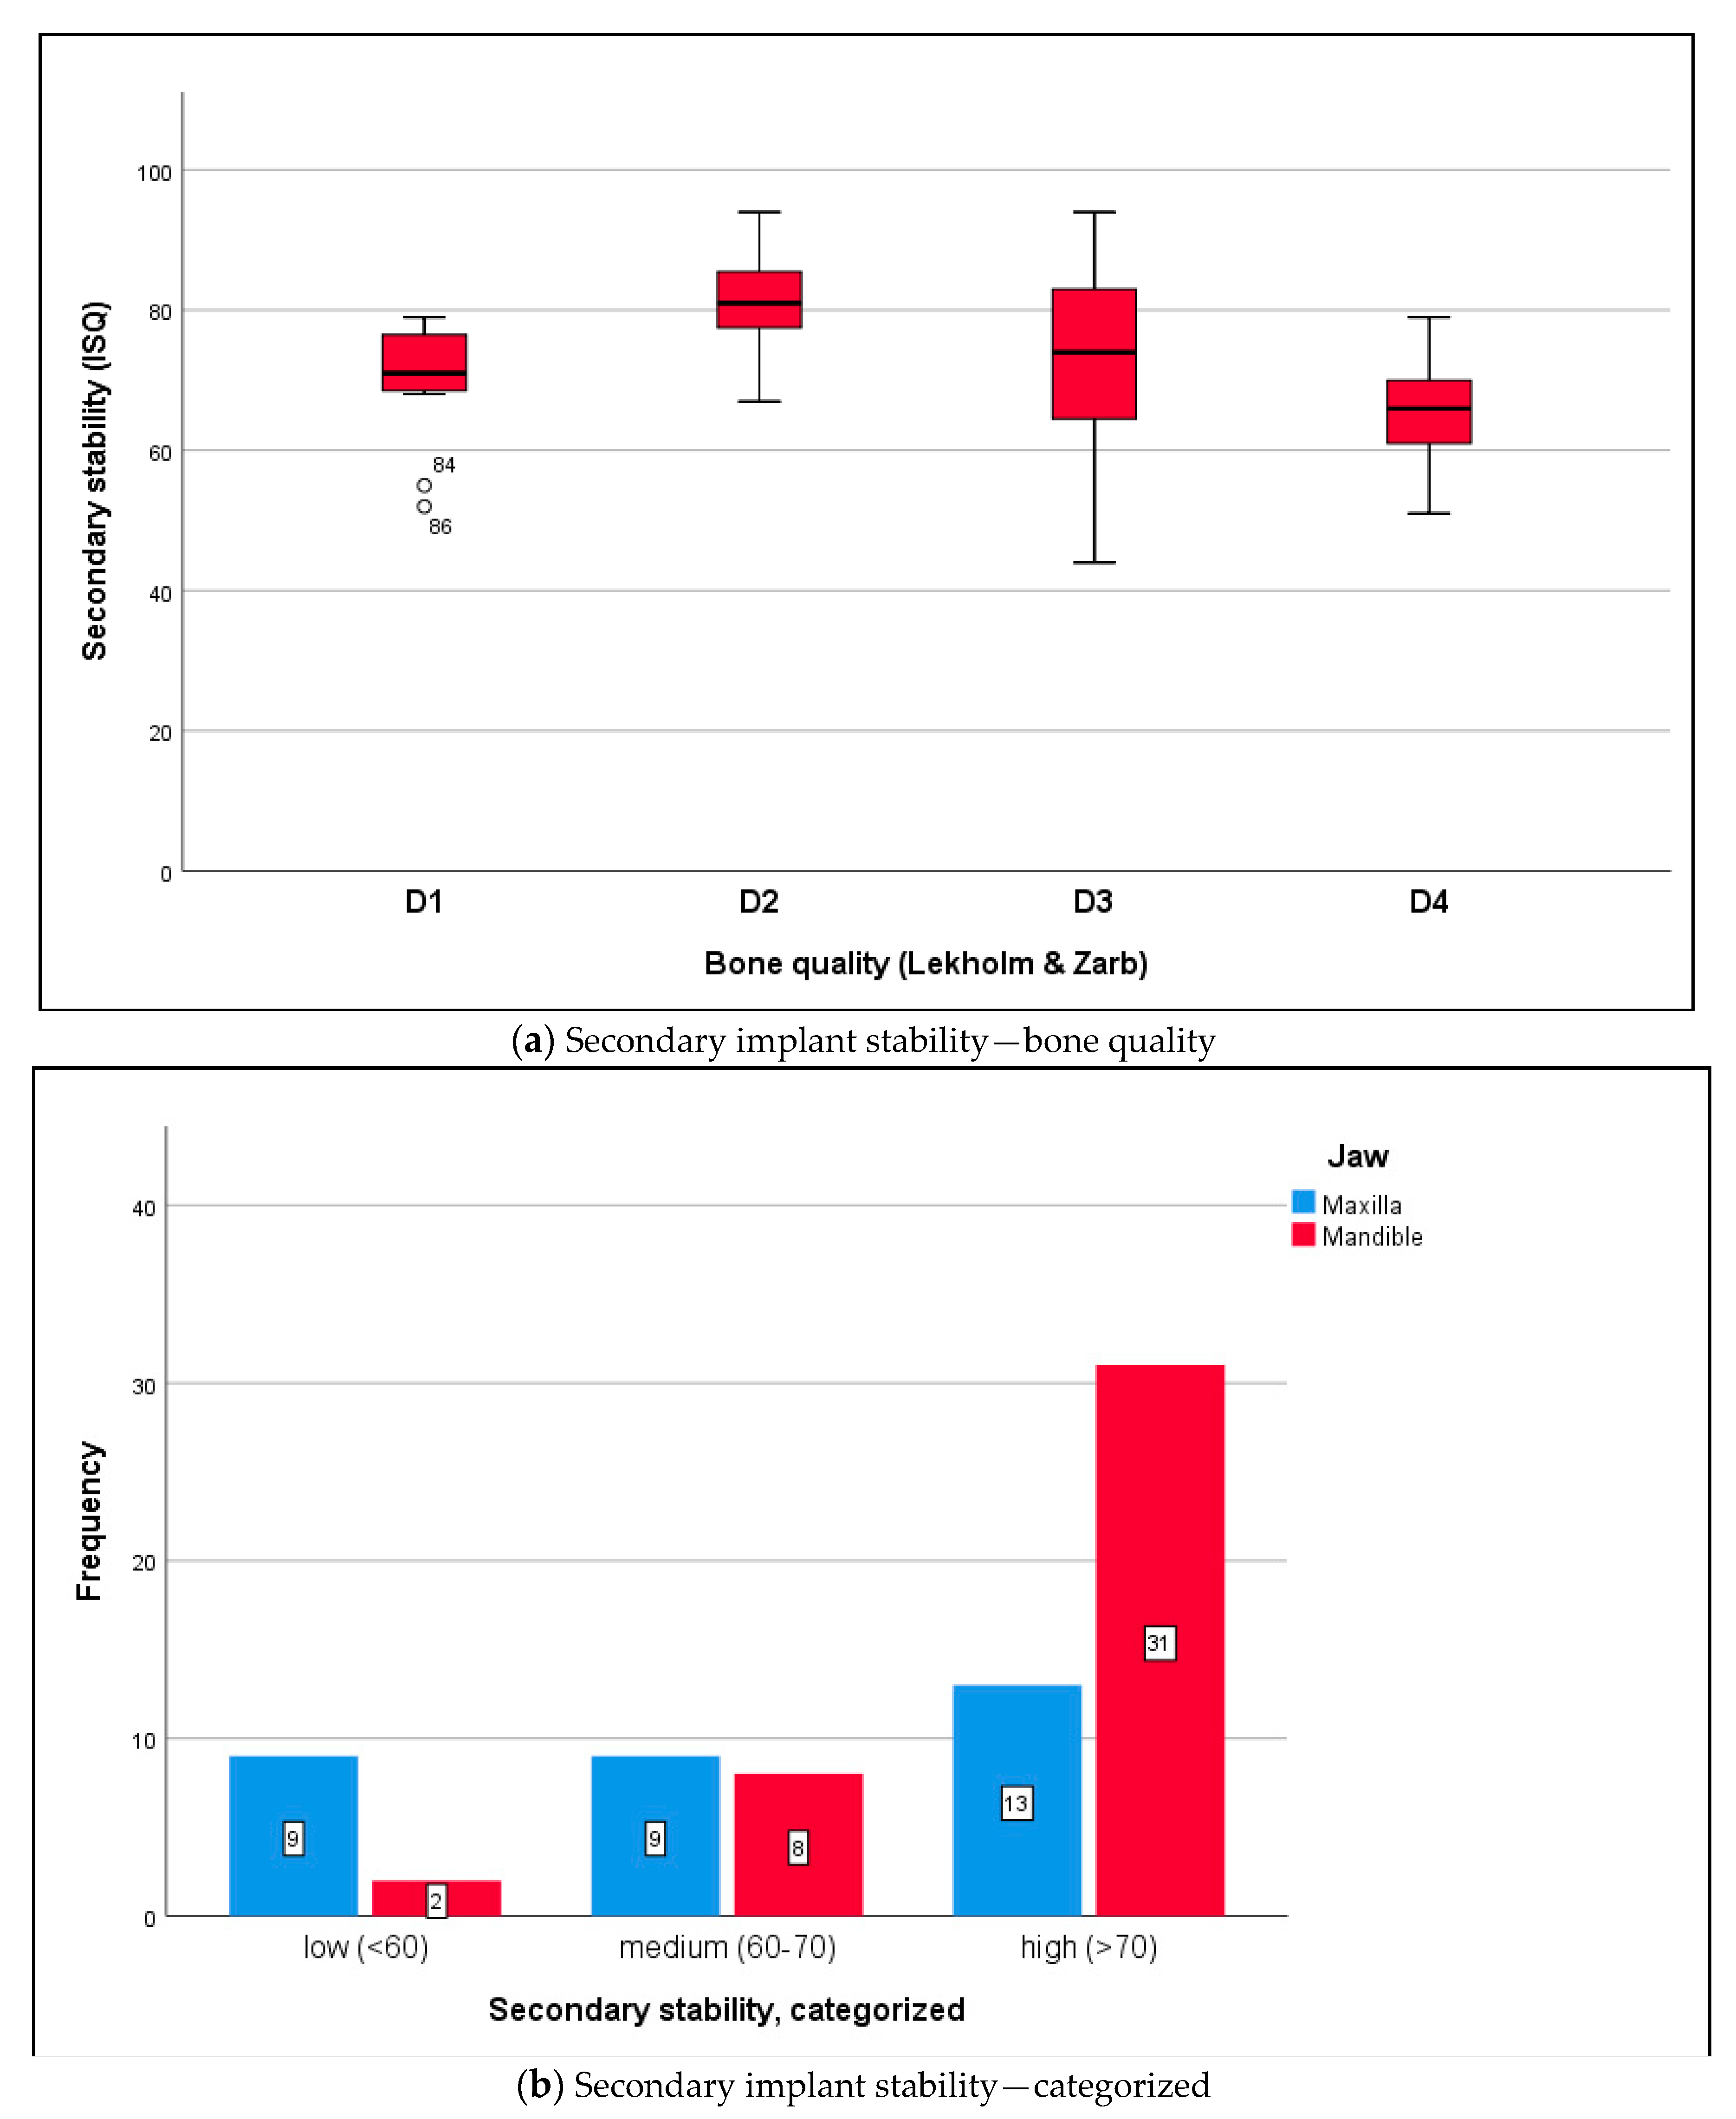

3.3. Biomechanical Implant Stability

4.2. Implant Stability under Difficult Conditions